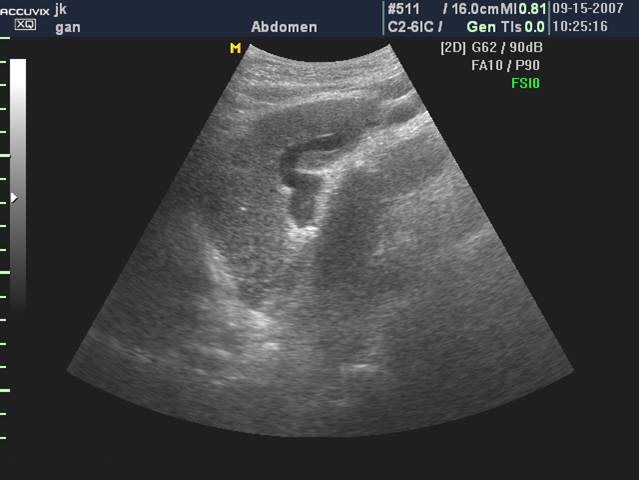

1、肝脏失去正常形态,体积较小。

2、肝脏包膜回声增强,表面高低不平,有的呈锯齿状。

3、肝实质回声增强、增粗、不均匀

①回声增强的光点,粗细不均。

②线状回声增强,可见短小粗线状增高回声。

③网状回声增强,各个方向的线条状回声汇成网状、网眼大小不等可小如绿豆、大如蚕豆。其间为病变较轻的肝细胞小岛及再生的肝结节,形成边缘不清晰的低回声区。

④片状回声增强,出现小片状回声增强区。

4、肝静脉变细

门静脉系统:主干扩张超过1.3cm ;脾静脉和肠系膜上静脉亦可扩张。

肝硬变声像

肝脏形态失常,缩小,边缘变钝

肝包膜增厚 呈锯齿状或凹凸状

肝实质回声增强、增粗、不均匀

门静脉系统扩张、脐静脉重开

脾大、腹水

胆囊壁水肿